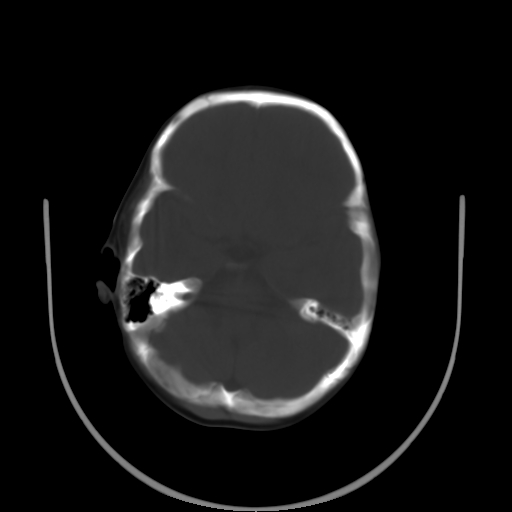

以下是引用深泽交通医院在2009-10-16 8:25:00的发言:[br]右眼环出血伴异物

以下是引用卜一在2009-10-16 15:01:00的发言:[br]右眼球挫裂伤伴异物!

以下是引用拾荒者在2009-10-17 18:38:00的发言:[br]鼻面部皮下积气,右侧睑缘及眼球壁高密度异物影,左侧眼球壁晶状体内侧缘处是圆形低密度影。低密度异物?应提请眼科医生注意。